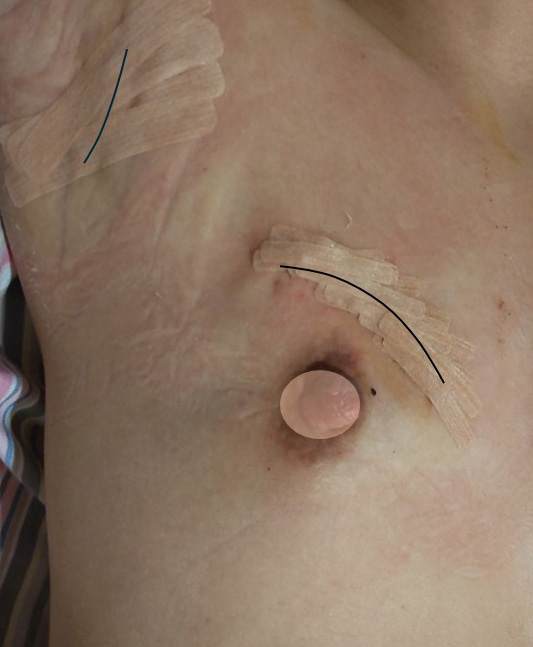

この症例の実際の傷(術後1日目)

センチネルリンパ節生検の傷(上)

乳腺切除の弧状切開(下)

変形は殆どなし